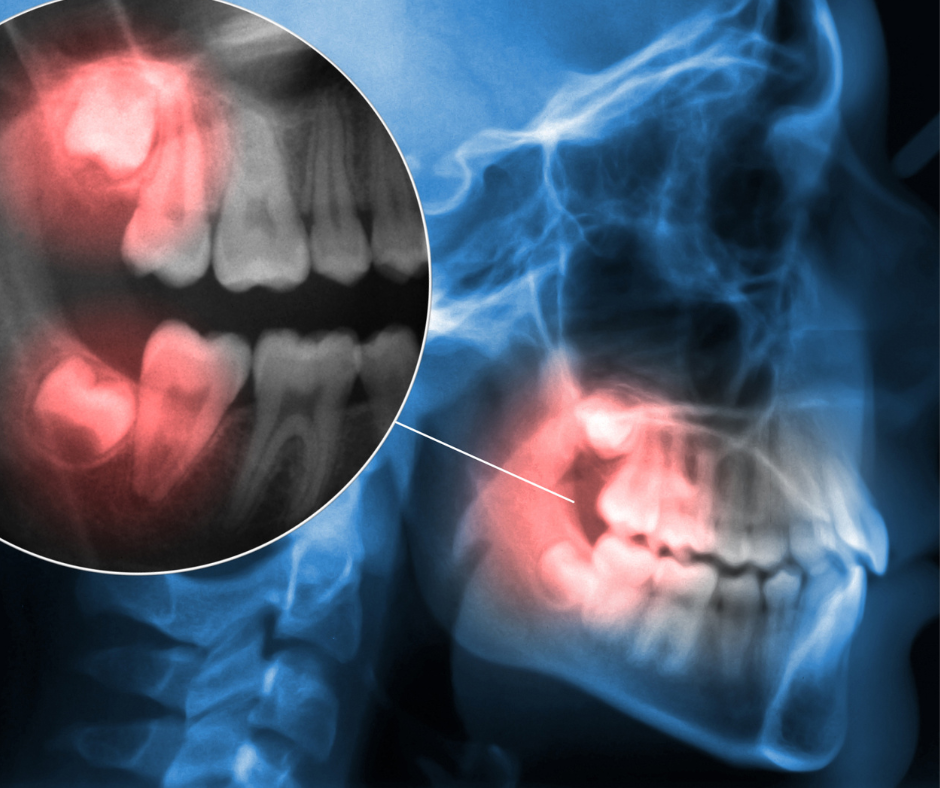

Wisdom tooth pain is one of the most common dental issues that we treat regularly; wisdom teeth don’t always cause issues for those who have them, but when they do it can cause major pain and disruption to everyday life. Here is our guide discussing all things wisdom teeth; from why we even have […]